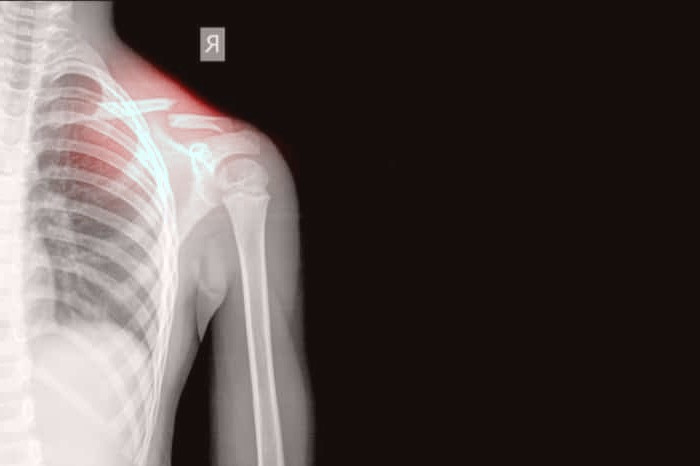

پوکی استخوان یک اختلال اسکلتی-عضلانی است که به طور عمده در سالمندان رخ میدهد و عمدتاً به دلیل کمبود مواد مغذی ضروری مانند ویتامینها و پروتئینها در رژیم غذایی فرد بروز میکند. ویژگی بارز این اختلال کاهش چشمگیر در استحکام و تراکم استخوانها است، امری که فرد را در معرض خطر افزایش قابل توجه ریسک شکستگی استخوان قرار میدهد. این وضعیت میتواند پیامدهای جدی برای سلامت و کیفیت زندگی سالمندان داشته باشد و نیازمند توجه و مدیریت پزشکی مناسب است.

پوکی استخوان یک بیماری متابولیک شایع استخوان است که در آن کاهش عمومی و شدید در توده استخوانی رخ می دهد. در این بیماری، عناصر تشکیل دهنده استخوان از نظر کیفیت تغییر نمی کنند، اما از نظر کمیت کاهش می یابند. این بیماری زمانی بروز می کند که کاهش توده استخوان بیش از حد سریع باشد. زنان بسیار بیشتر از مردان مبتلا به پوکی استخوان می شوند و با افزایش سن، احتمال بروز این بیماری نیز افزایش می یابد.